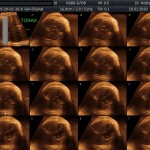

Los objetivos más importantes de esta ecografía son la evaluación de:

- La anatomía fetal: Diagnostico de Malformaciones Estructurales de aparición tardía (displasias esqueléticas, alteraciones cardíacas pequeñas, alteraciones de la vía urinaria y obstrucciones intestinales).